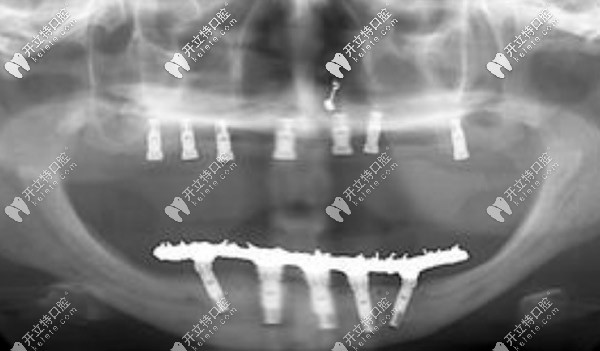

【全口allon4/6即刻負重技術】

一般需要8顆或12顆種植體,可恢復全口牙,當然這個費用比較高,韓系的價格一般在12萬元起

種植牙的優(yōu)勢就不過多介紹了,ALLon4與普通的種植技術不同在于,利用斜拉式的力學原理,可以避免上頜竇及下頜神經(jīng)等危險區(qū),當天即可戴牙吃東西。美中不足則是該技術對醫(yī)生的技術要求較高,且費用較高。